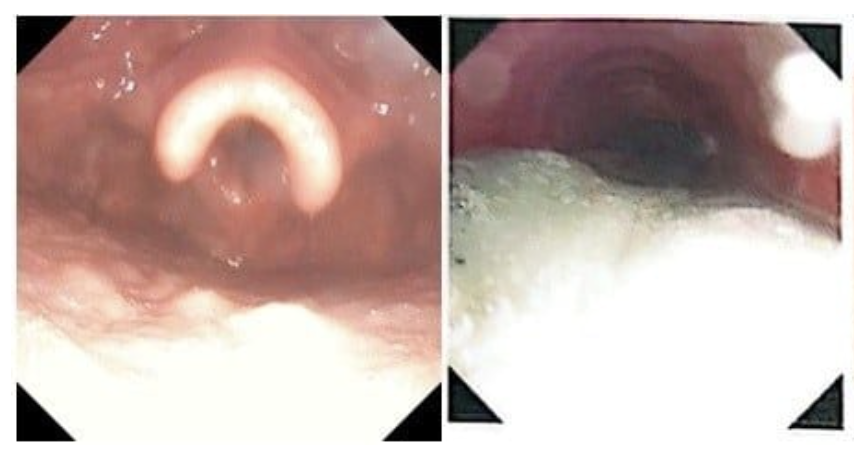

Chất tiết có rất nhiều muội than, tro bụi từ phổi của người bệnh được hút ra bằng phương pháp nội soi phế quản ống mềm tại giường

Nhận định nguy cơ cao tổn thương đường thở do hít phải tro bụi và muội than, các bác sĩ chuyên khoa hô hấp đã triển khai kỹ thuật nội soi phế quản ống mềm tại giường bệnh, kết hợp rửa phế quản ngay trong ngày nhập viện và duy trì nhiều ngày liên tiếp. Thủ thuật này giúp loại bỏ lượng lớn muội than, dịch tiết và chất độc trong đường thở, góp phần giảm viêm và cải thiện chức năng hô hấp.

Sau 8 ngày điều trị tích cực, từ tình trạng hôn mê, phải thở máy và hỗ trợ đa cơ quan, hai bệnh nhân đã hồi phục tốt, tự thở được, ăn uống và sinh hoạt bình thường. Cả hai đã được xuất viện và tiếp tục tái khám theo lịch theo dõi.